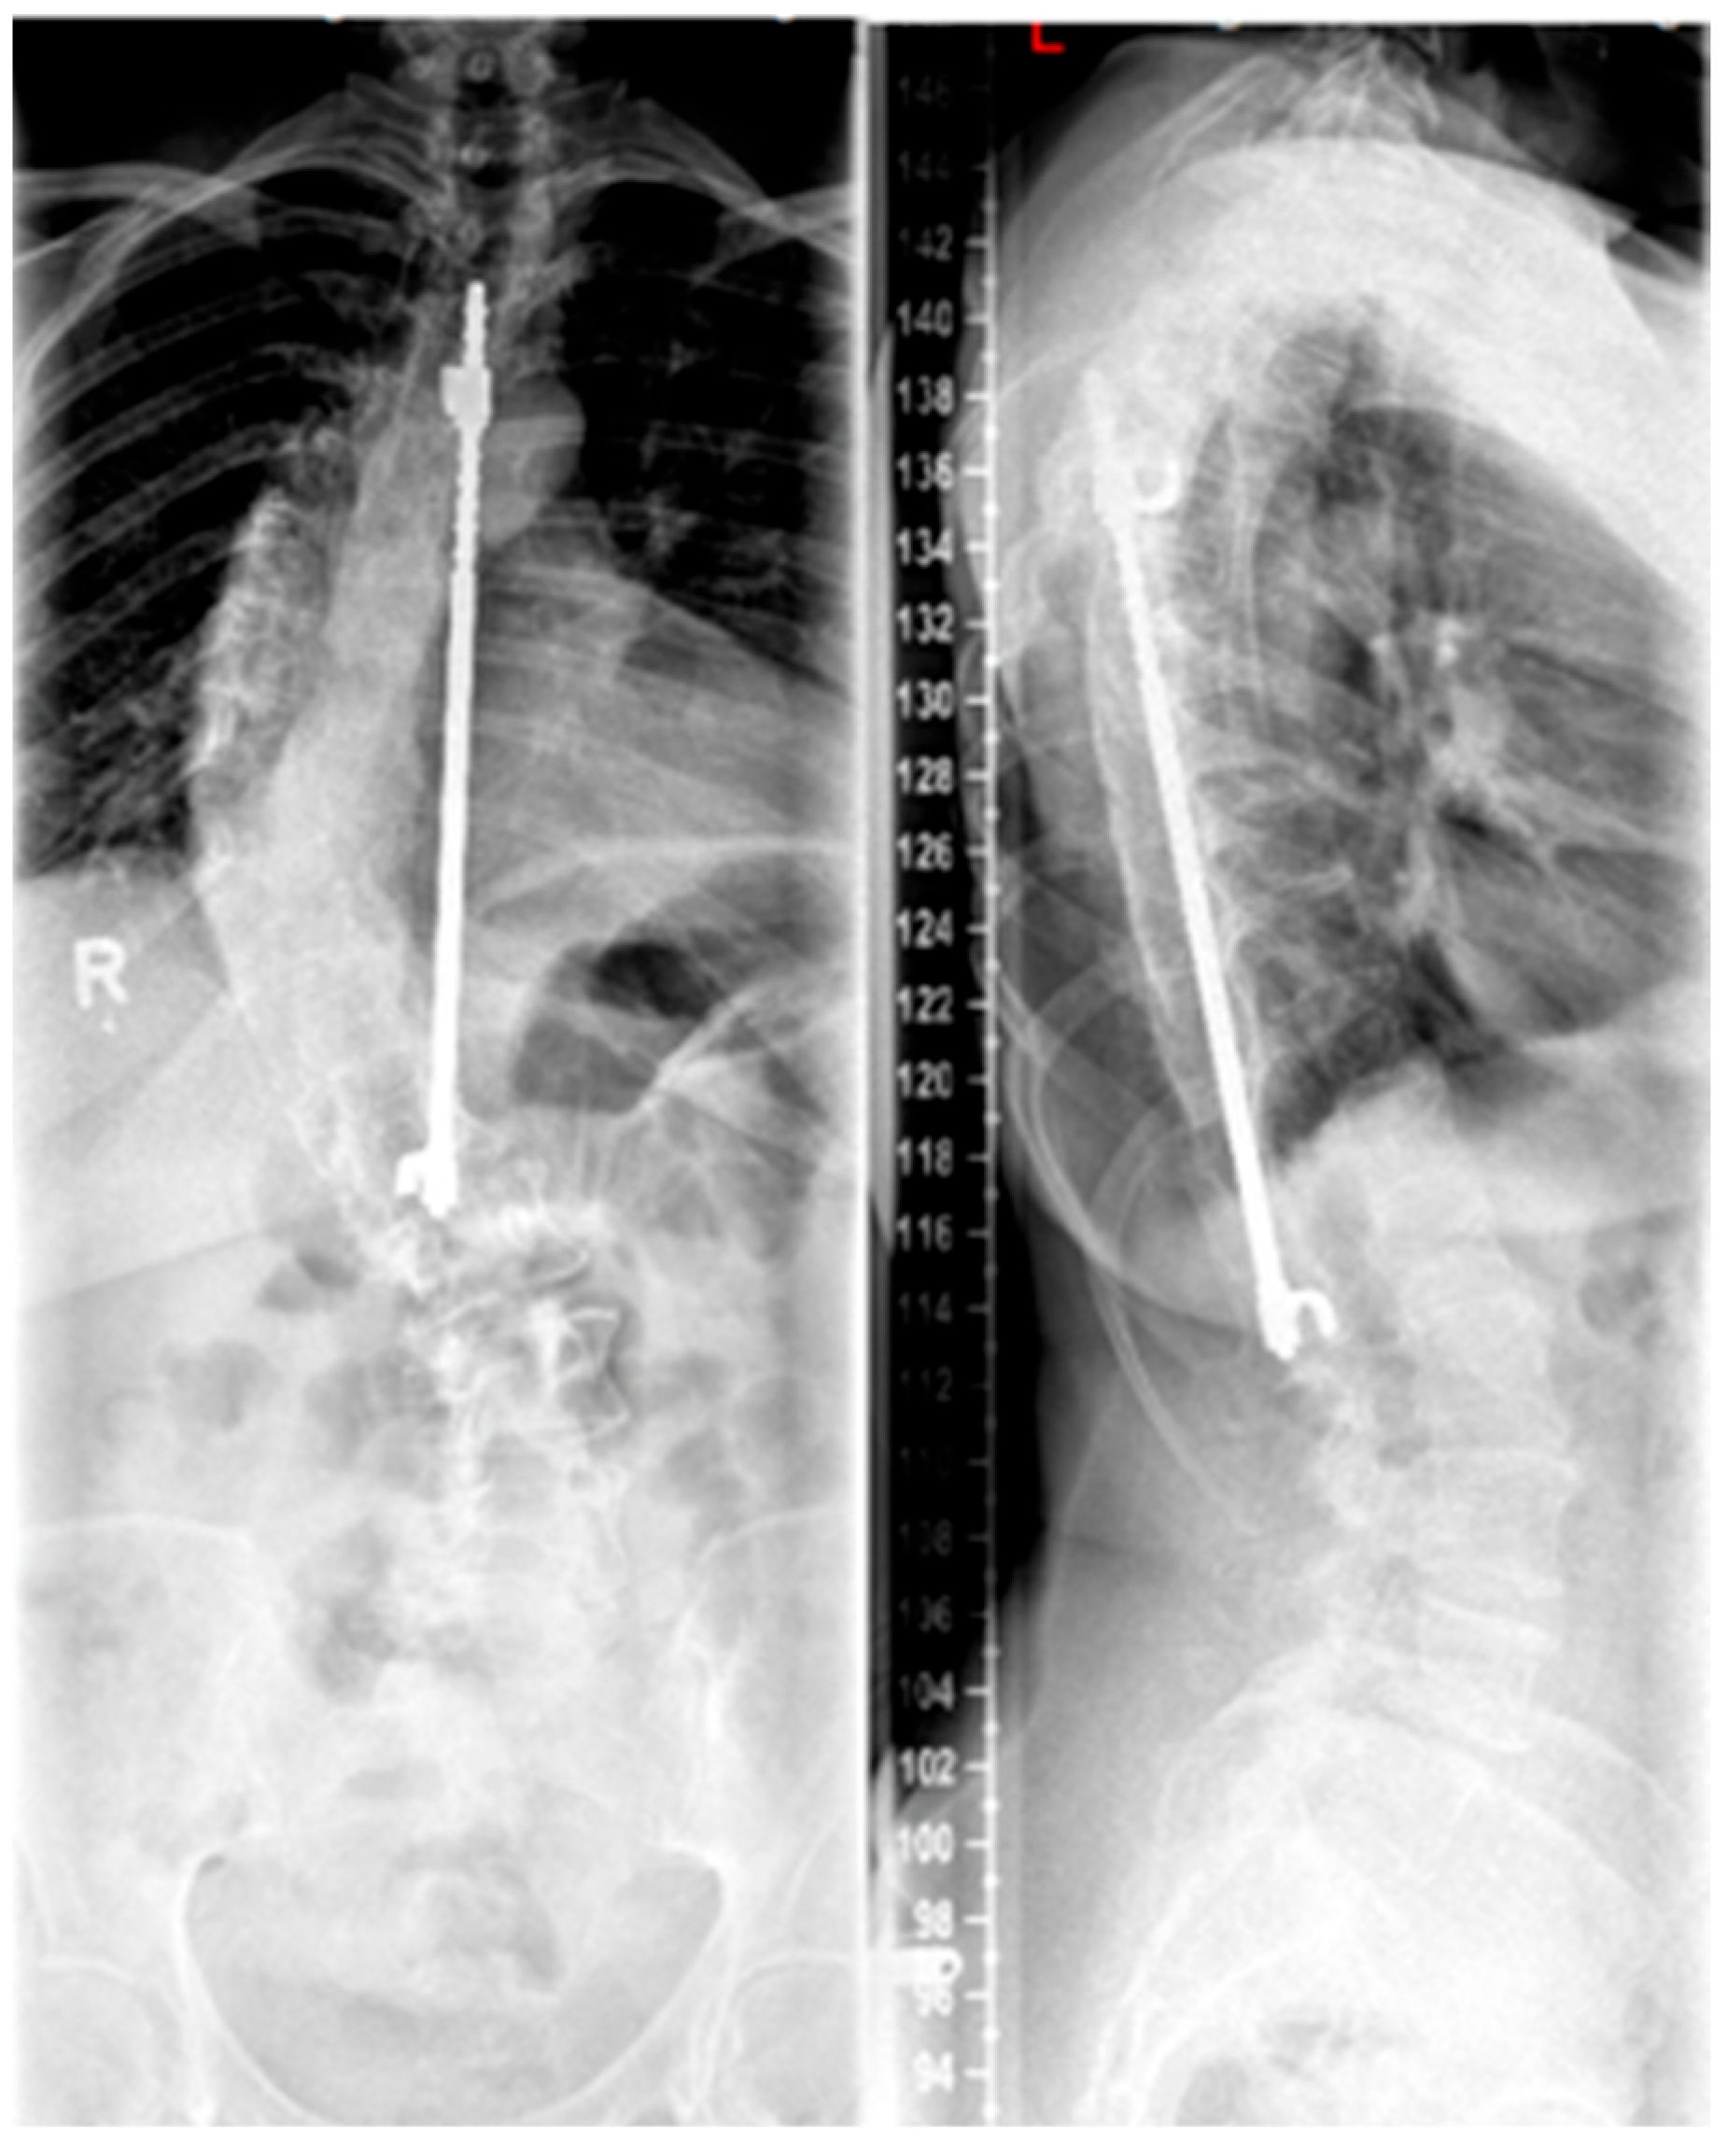

Figure 3. Patient post-Harrington instrumentation from T4 to L1 performed in 1980 (reprinted with permission [10]).